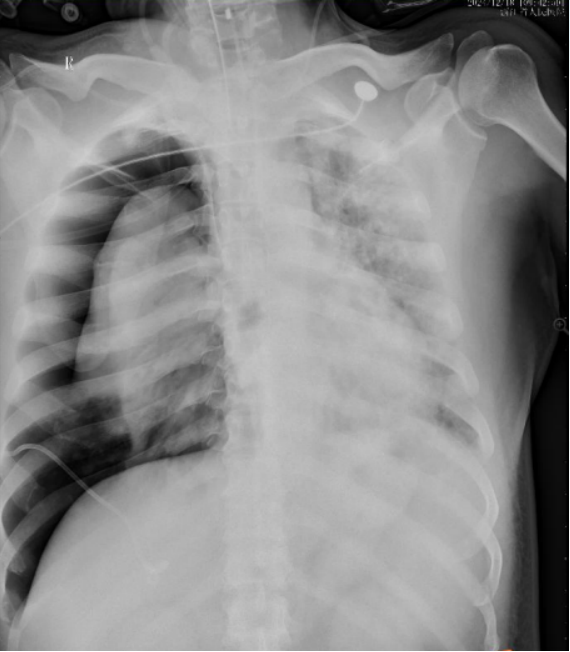

胸部增强CT(图2)胸部CT较前进展。两肺多发散在斑片状结节状密度增高影,肺内见多发空洞/支气管扩张,壁厚。未见明显骨折及脱位征象,胸部及心包未见明显积气积液征象,纵隔未见明显积气、积液及占位征象。

图片

2  患者转入ICU前后胸部CT对比